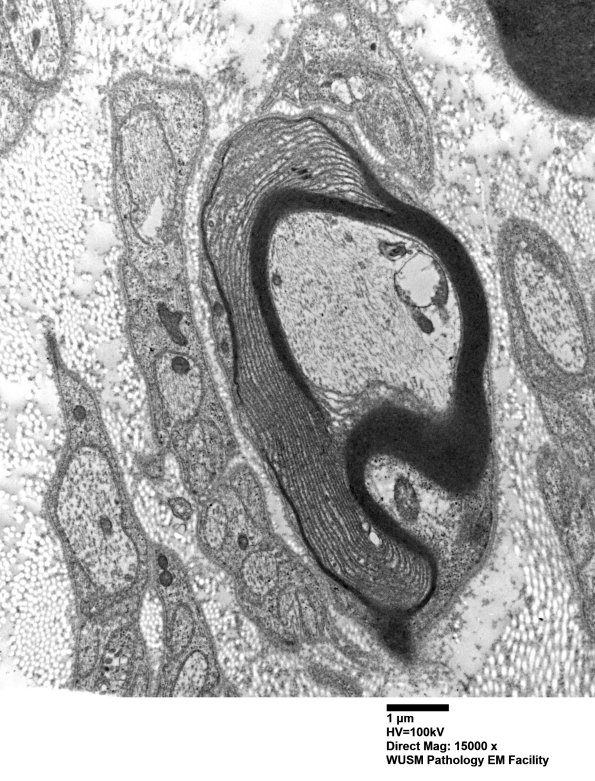

3A2A,B Patchy UCM envelopes much of the circumference of the axon. (electron micrographs)